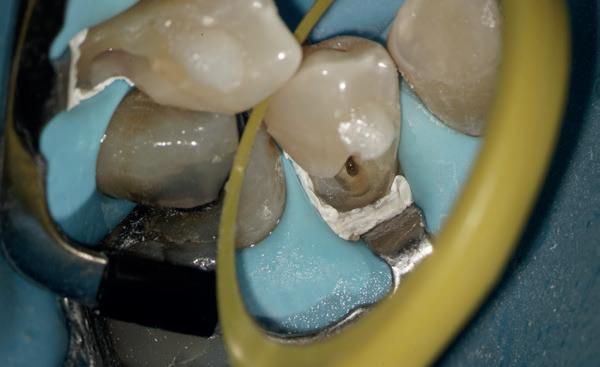

Het isoleren van het werkgebied is belangrijk. Op deze manier krijgt de behandelaar meer controle over het werkgebied en is werken onder microscopisch zicht mogelijk. Eventueel kan er gebruik gemaakt worden van de ‘split dam techniek’, zodat het subgingivale gebied toegankelijker is. Het (opnieuw) plaatsen van het cofferdamvel na preparatie is ook een mogelijkheid (afbeelding 1 en 2).

Stap 2: Preparatie van element en gingiva

Verwijder carieus tandweefsel en maak bij twijfel gebruik van een cariësdetector. In veel gevallen zal het voorkomen dat je subgingivaal eindigt. Gingiva dat in de preparatie ligt kun je verwijderen met bijvoorbeeld een elektrotoom. Ikzelf maak gebruik van

een draadloze warmtespreader, de Superendo Alpha (afbeelding 3 en 4).